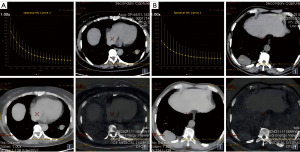

The mean of the measurements was taken, with consistency testing showing an intraclass correlation coefficient (ICC) >0.90. Typical patient DECT parameter measurements are shown in Figure 2.